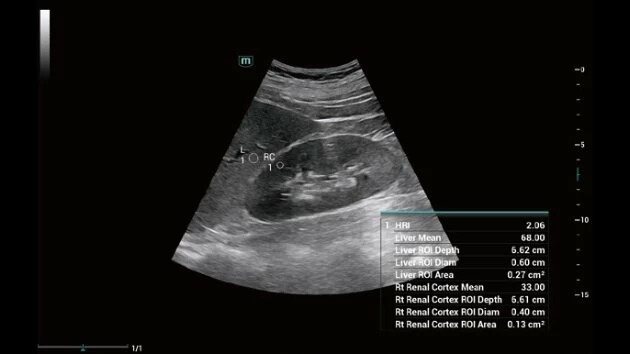

Ультразвуковой аппарат Mindray Consona N7 принадлежит к категории устройств экспертного класса и предназначен для проведения широкого спектра общей диагностики. Благодаря высокому уровню визуализации, он активно применяется в кардиологии, а также для гинекологических исследований.

• Широкий спектр клинических исследований

• Расширенные возможности визуализации различных органов и тканей

Общая визуализация:

Да